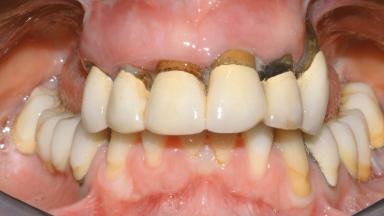

Conventional Loading of Eight Implants in the Maxilla and Final Restoration with a Full-Arch Gold-Ceramic FDP

A 35-year-old Caucasian female presenting with advanced periodontal disease involving both the maxillary and the mandibular dentition was referred for evaluation. The patient, a non-smoker in good general health, requested treatment for recurrent periodontal abscesses, tooth mobility, and discomfort during chewing, as well as restoration of her missing teeth with a fixed prosthesis to improve mastication and esthetics. All residual maxillary teeth exhibited plaque deposits, deep pockets, bleeding on probing, and class III mobility and were evaluated as hopeless. All residual mandibular teeth except tooth 37 could be maintained after periodontal therapy.